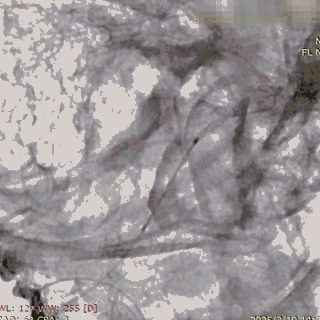

支架及支架微导管到位。

支架头端打开。

支架远端打开造影。

等张释放,支架中段打开至50%释放标记点。

支架中段打开造影。

支架近端打开,完全释放。

支架完全释放造影。

术后即刻造影。

术后重建。